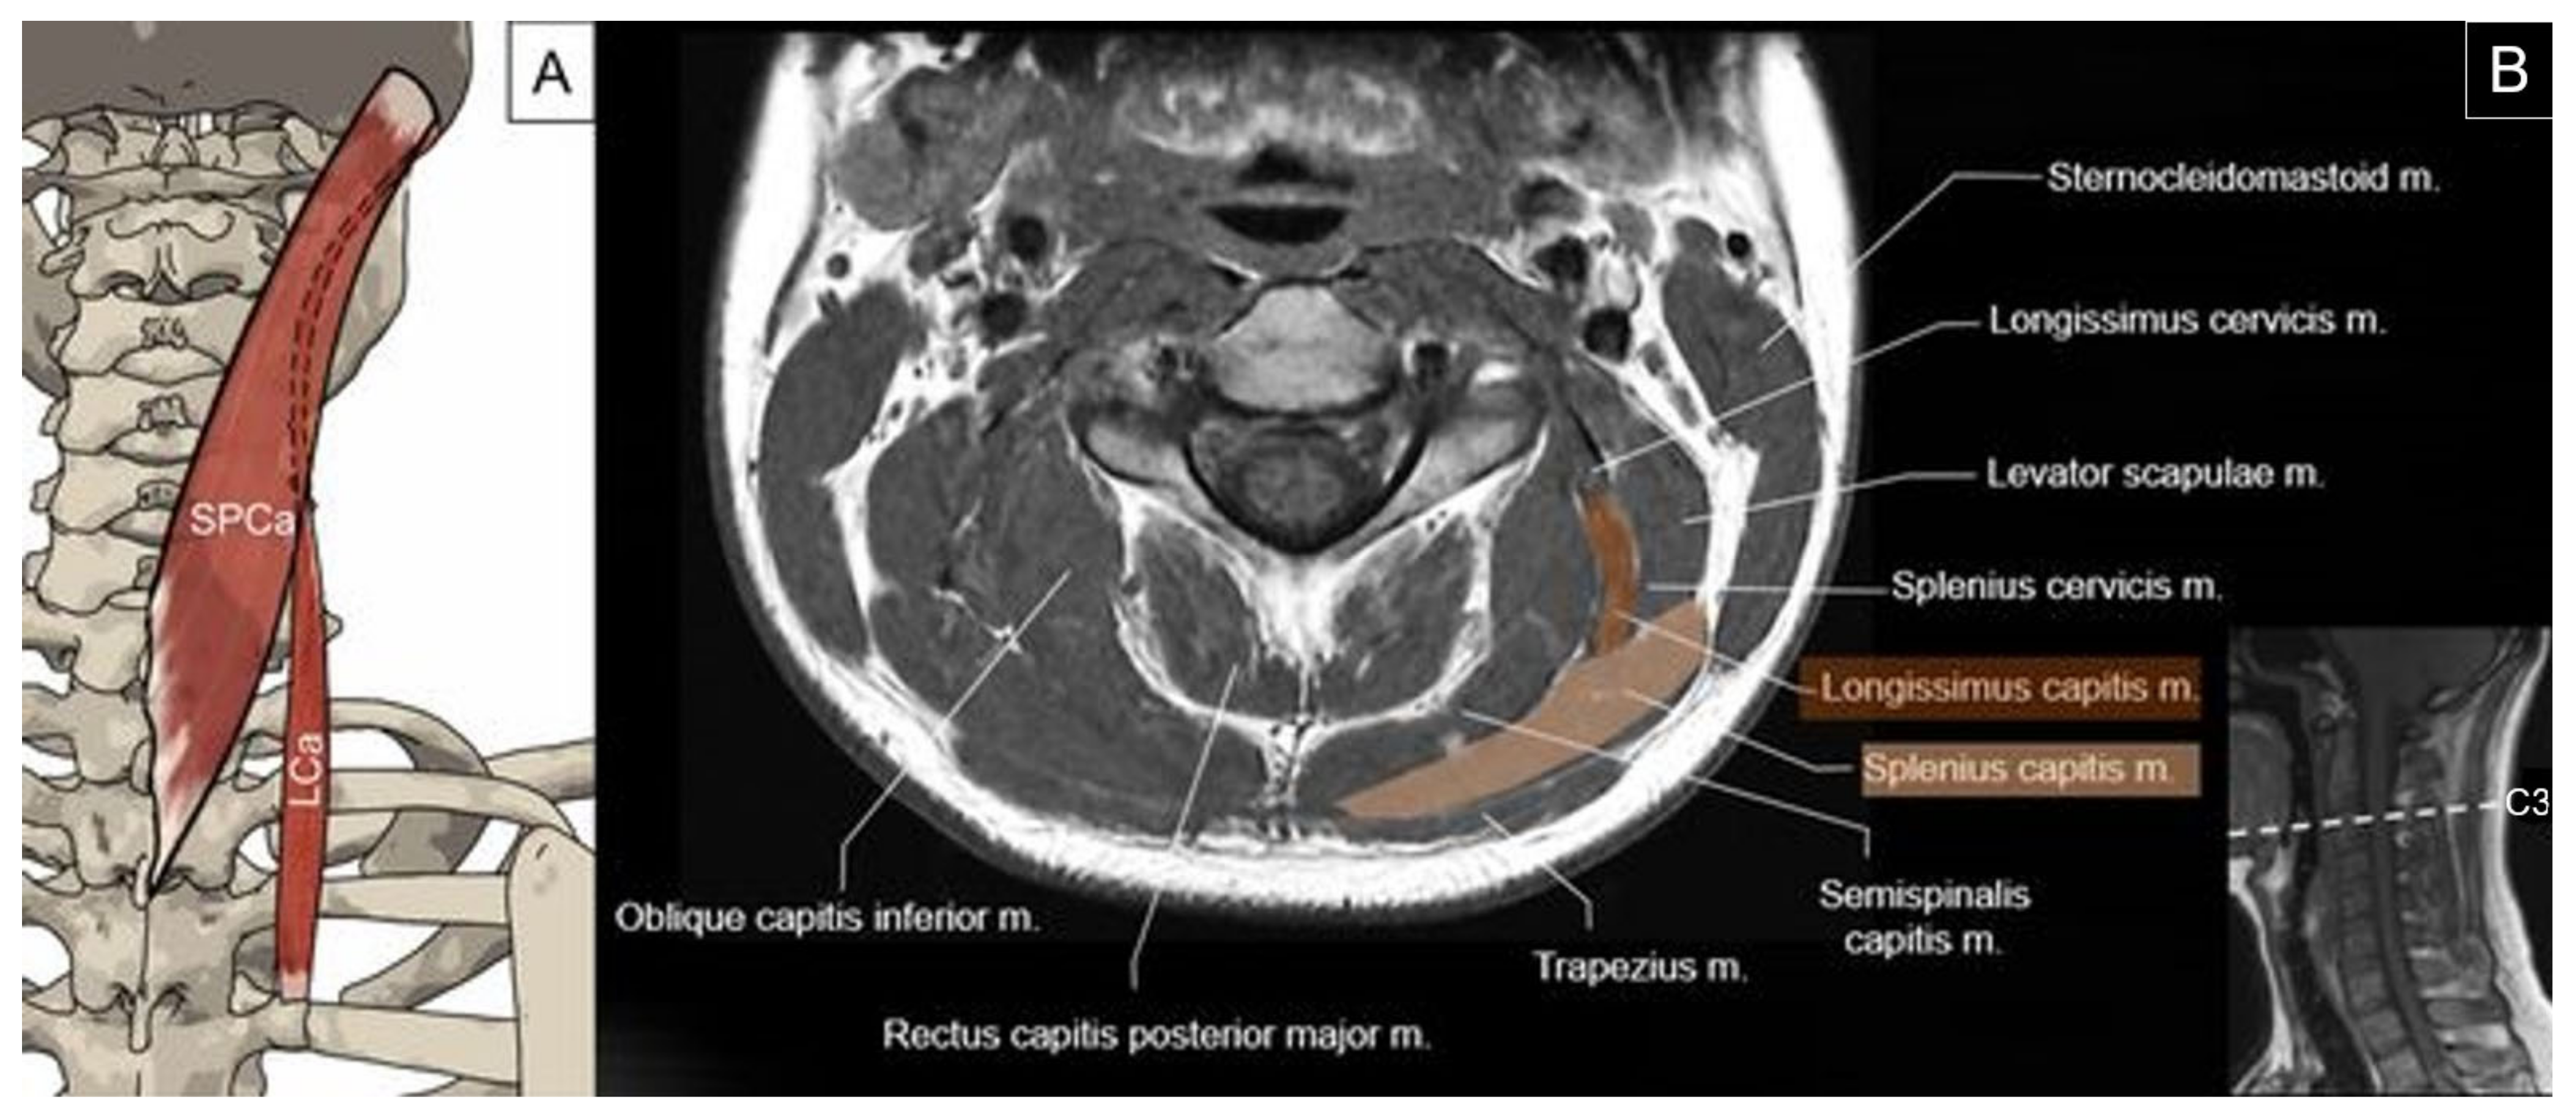

4.1. Splenius Capitis and Longissimus Capitis

4.1.1. Anatomy

4.1.2. Sonographic Scanning

4.1.3. Clinical Relevance